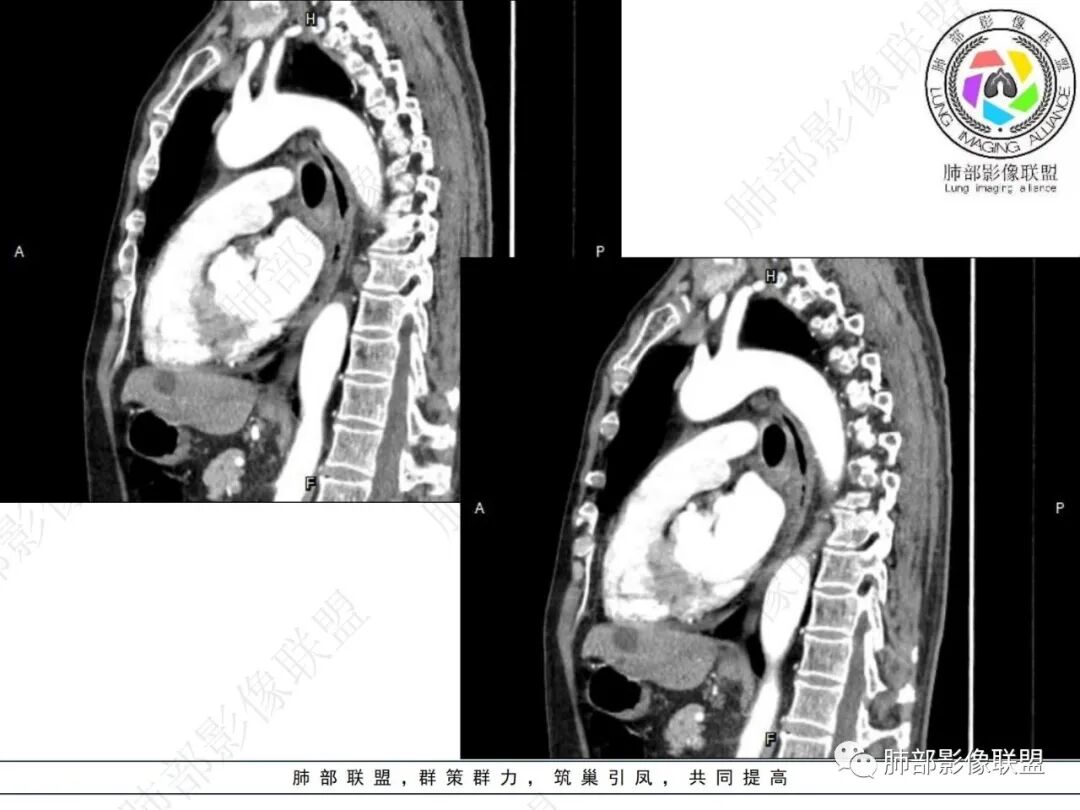

右肺下叶沿肺叶肺段分布斑片、条片状影,以下叶背段为显,边缘模糊,内可见支气管走行,局部支气管管壁增厚,右侧胸腔少量积液。纵隔隆突下可见不均匀软组织密度影,与周围结构分界不清,内见气体密度影,与食管及相邻右肺支气管之间未显示通道。邻近食管下段壁明显不规则增厚,增强后食管管壁明显不均匀强化,可见线样强化的连续完整粘膜影。

3.综合分析:

右肺下叶片影,气道相关,符合感染性病变。纵隔隆突下软组织密度影,异常气体影,长病程,起病缓慢,提示存在气管或食管瘘。食管镜未见明显新生物形成,临床未提供进食或饮水呛咳临床表现,综合分析应该考虑支气管瘘的形成。

对比患者3月份的CT图,原隆突下存在增大钙化淋巴结,现在出现气体影,且钙化显示不清,应想到淋巴结结核破溃成瘘可能性。